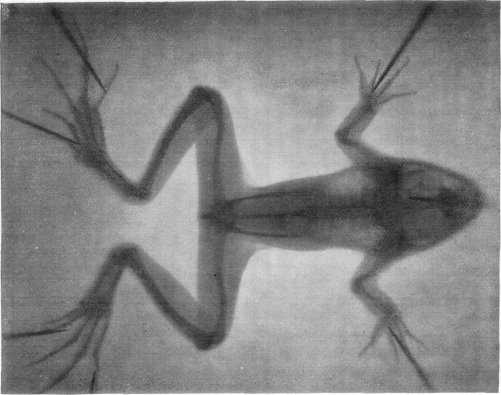

SKELETON OF A FROG, PHOTOGRAPHED THROUGH THE FLESH. THE SHADINGS INDICATE, IN ADDITION TO THE BONES, ALSO THE LUNGS AND THE CEREBRAL LOBES.

From a photograph by Professors Imbert and Bertin-Sans; reproduced by the courtesy of the "Presse Medicale," Paris. In taking this photograph the experiment was tried of using a diaphragm interposed between the Crookes tube and the plate; and the superior clearness obtained is thought to result from this.